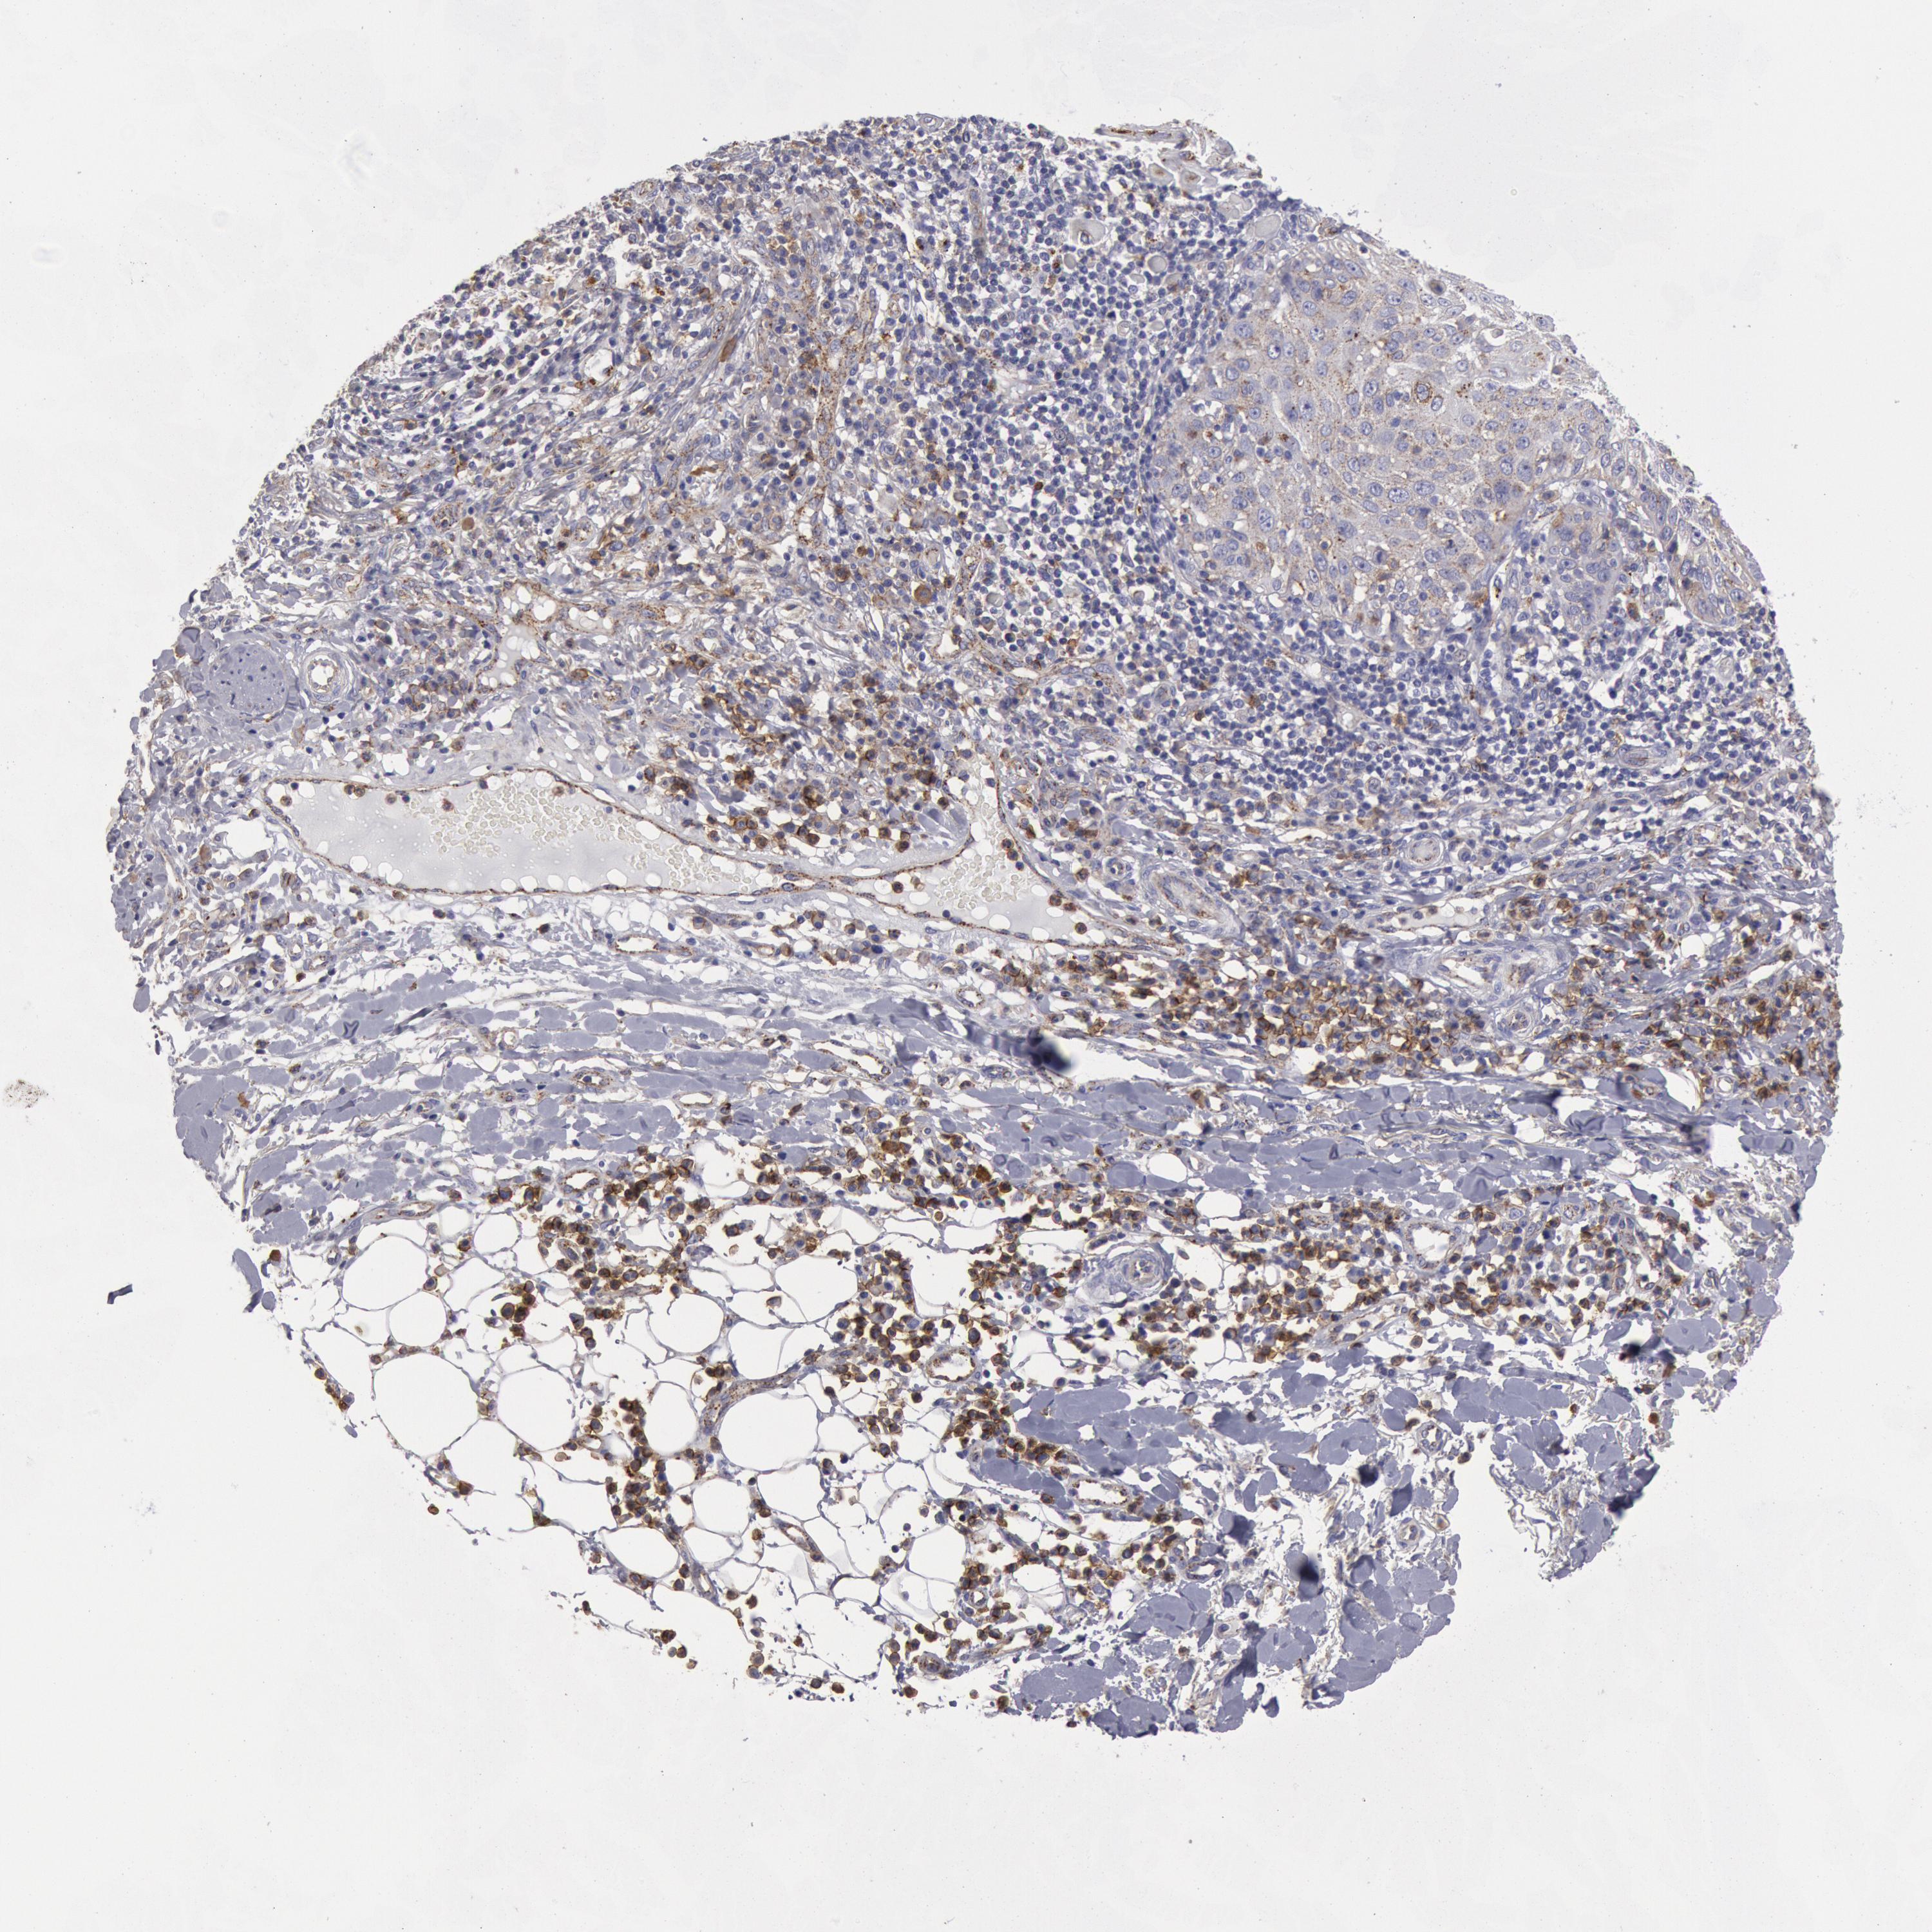

SKIN CANCER - Protein expressioni

A mouse-over function shows sample information and annotation data. Click on an image to view it in a full screen mode. Samples can be filtered based on level of antibody staining by selecting one or several of the following categories: high, medium, low and not detected. The assay and annotation is described here.

Antibody stainingi

Antibody staining in the annotated cell types in the current human tissue is reported as not detected, low, medium, or high, based on conventional immunohistochemistry profiling in selected tissues. This score is based on the combination of the staining intensity and fraction of stained cells.

Each image is clickable and will lead to virtual microscopy that enables deeper exploration of all samples and also displays staining intensity scores, fraction scores and subcellular localization as well as patient and tissue information for each sample.

Antibody HPA001393

Squamous cell carcinoma, NOS